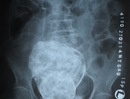

Liên quan đến trường hợp mang “thai đá” của cụ Sáu, các bác sỹ đầu ngành của tỉnh Khánh Hòa đã hội chẩn liên viện lần thứ 2 và thống nhất sẽ mổ cấp cứu trong trường hợp...